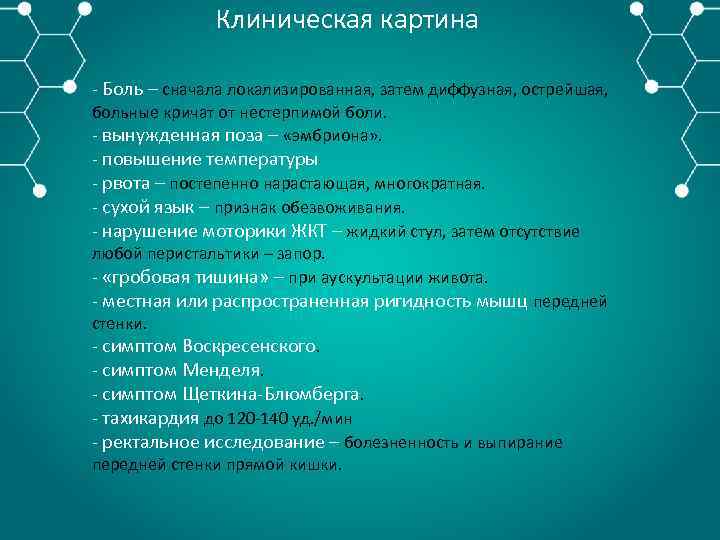

Клиническая картина Боль – сначала локализированная, затем диффузная, острейшая, больные кричат от нестерпимой боли. вынужденная поза – «эмбриона» . повышение температуры рвота – постепенно нарастающая, многократная. сухой язык – признак обезвоживания. нарушение моторики ЖКТ – жидкий стул, затем отсутствие любой перистальтики – запор. «гробовая тишина» – при аускультации живота. местная или распространенная ригидность мышц передней стенки. симптом Воскресенского. симптом Менделя. симптом Щеткина Блюмберга. тахикардия до 120 140 уд. /мин ректальное исследование – болезненность и выпирание передней стенки прямой кишки.